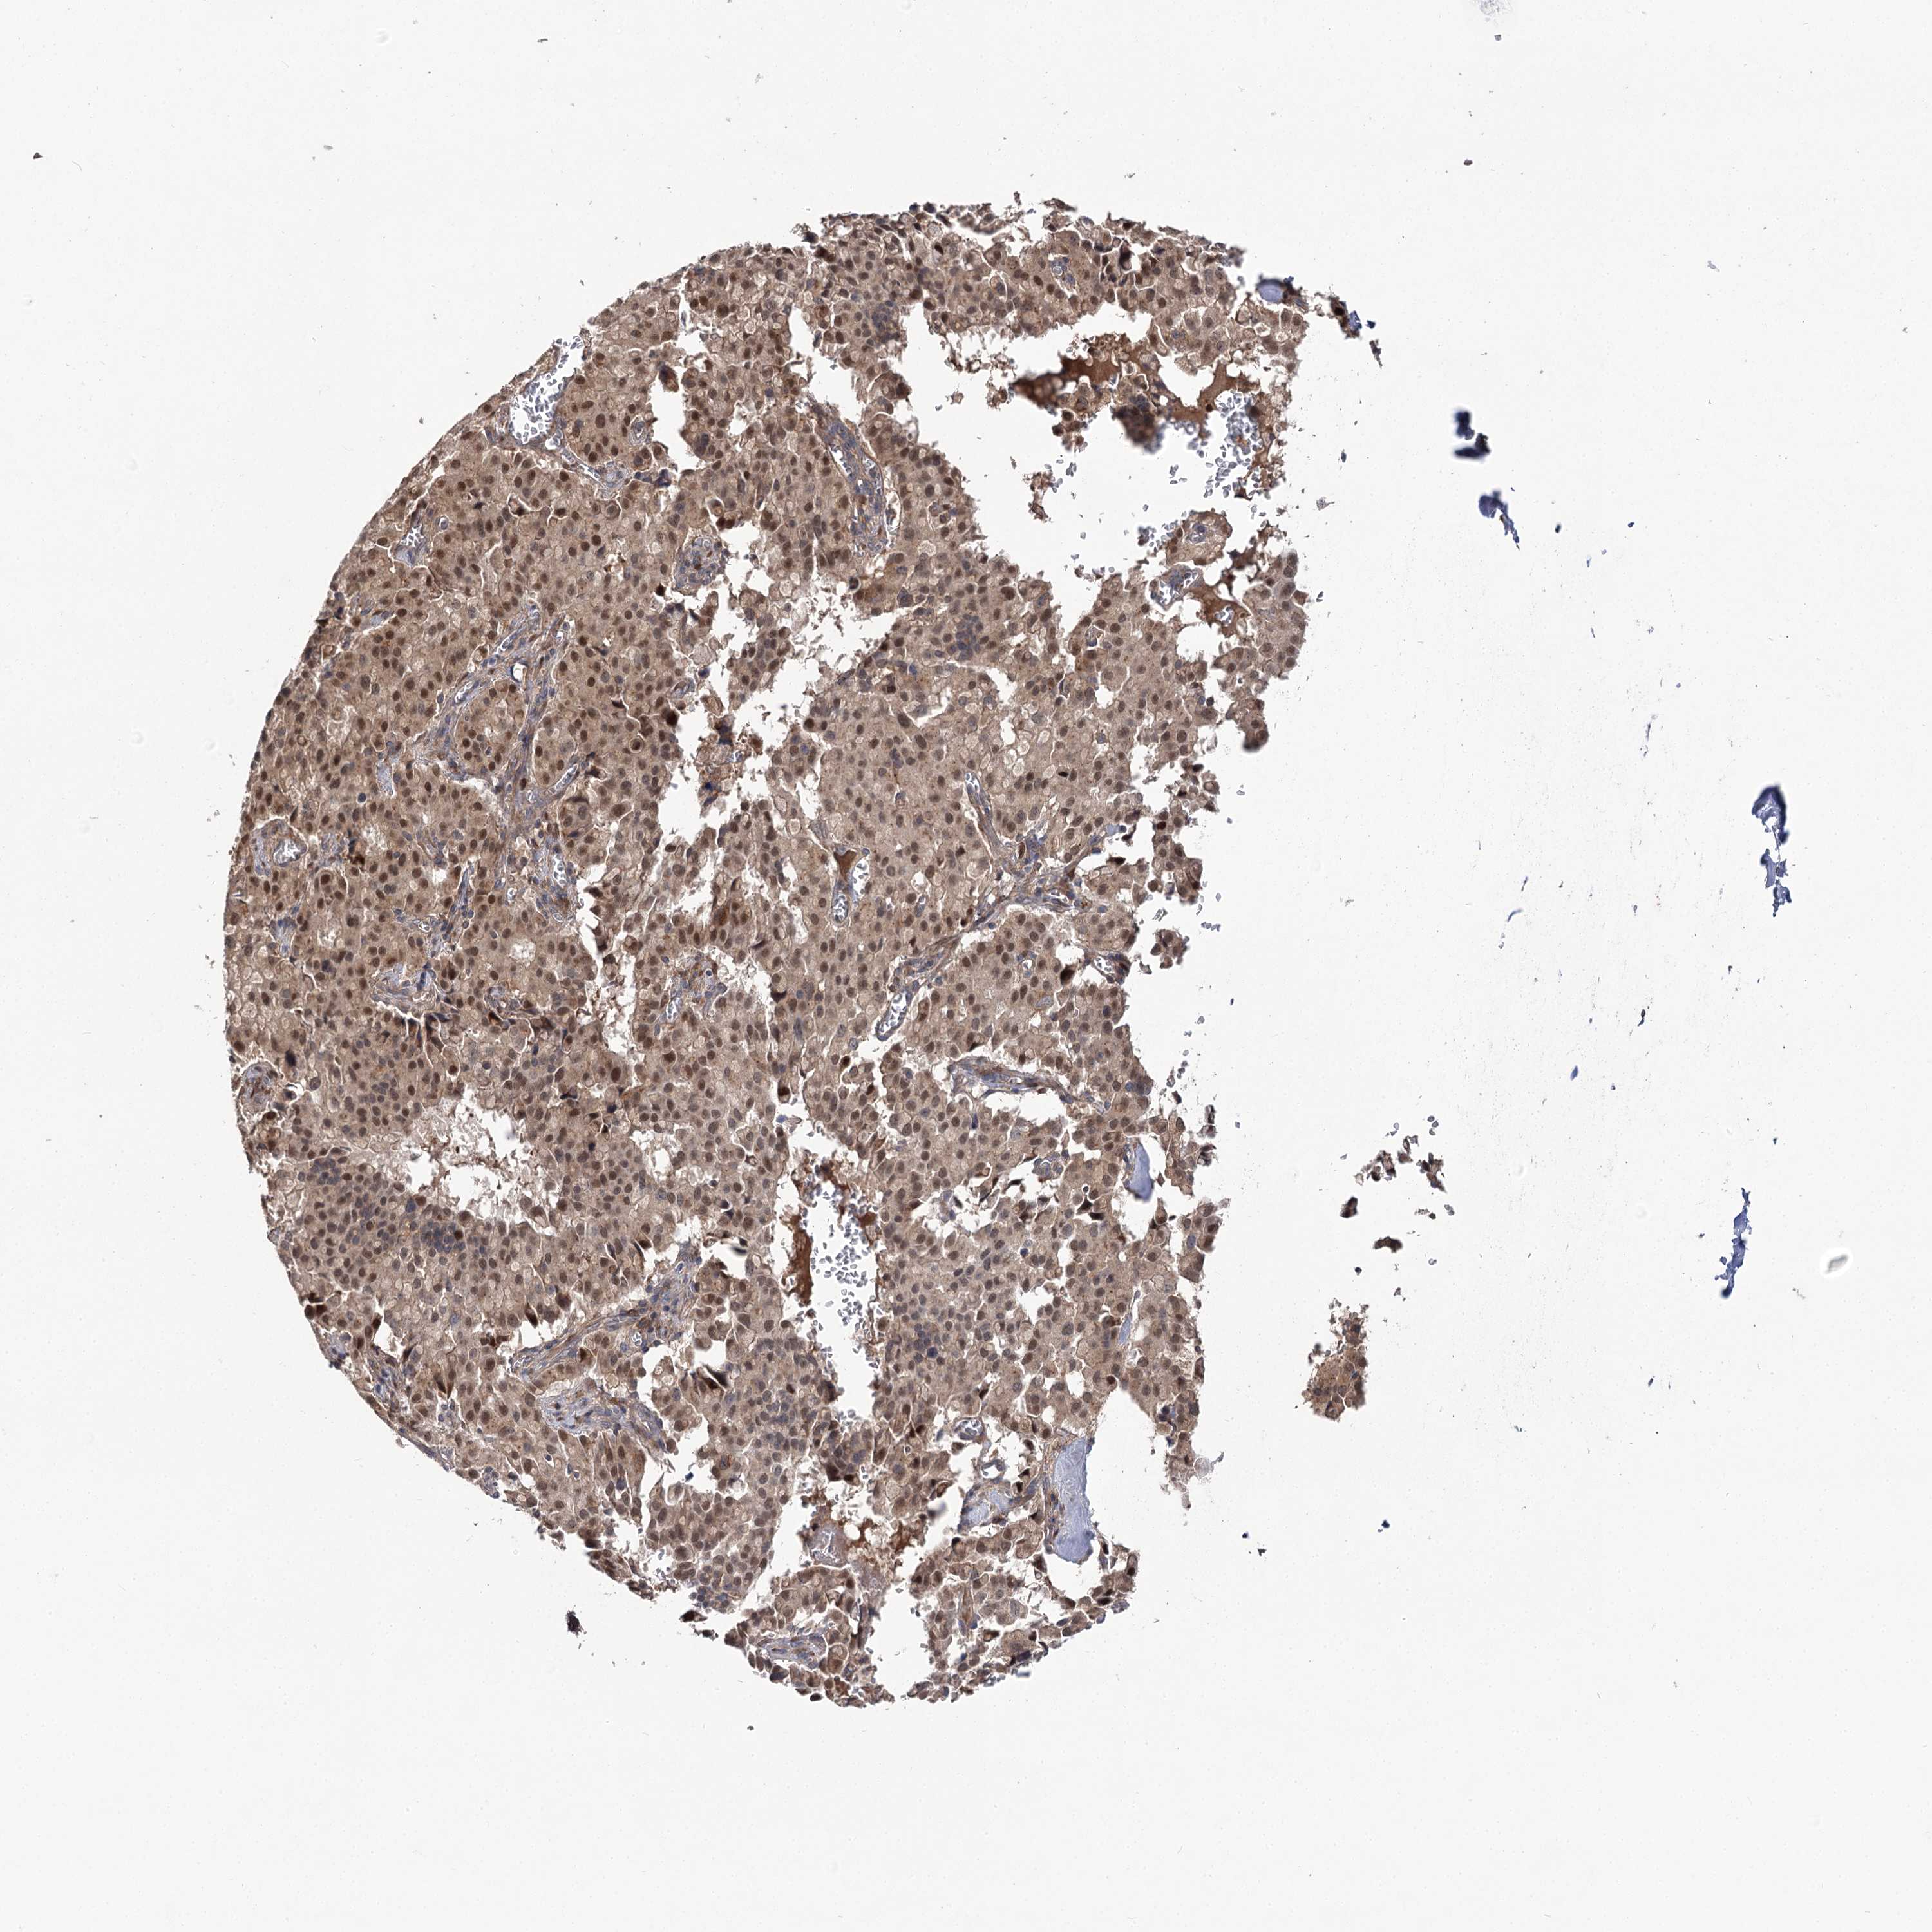

PANCREATIC CANCER - Protein expressioni

A mouse-over function shows sample information and annotation data. Click on an image to view it in a full screen mode. Samples can be filtered based on level of antibody staining by selecting one or several of the following categories: high, medium, low and not detected. The assay and annotation is described here.

Note that samples used for immunohistochemistry by the Human Protein Atlas do not correspond to samples in the TCGA dataset.

Antibody stainingi

Antibody staining in the annotated cell types in the current human tissue is reported as not detected, low, medium, or high, based on conventional immunohistochemistry profiling in selected tissues. This score is based on the combination of the staining intensity and fraction of stained cells.

Each image is clickable and will lead to virtual microscopy that enables deeper exploration of all samples and also displays staining intensity scores, fraction scores and subcellular localization as well as patient and tissue information for each sample.

Antibody HPA038557

Antibody HPA038558

Staining

High

Medium

Low

Not detected

Intensity

Strong

Moderate

Weak

Negative

Quantity

>75%

75%-25%

<25%

None

Location

Nuclear

Cytoplasmic/membranous

Cytoplasmic/membranous,nuclear

Adenocarcinoma, NOS